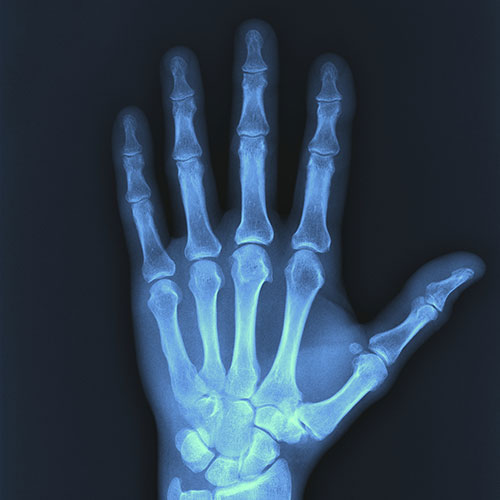

2D Image Modalities

X-Ray